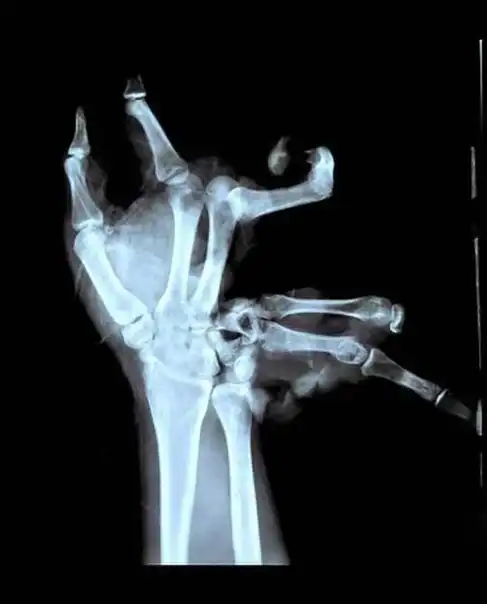

Парень держал в руке самодельную взрывчатку, та взорвалась.